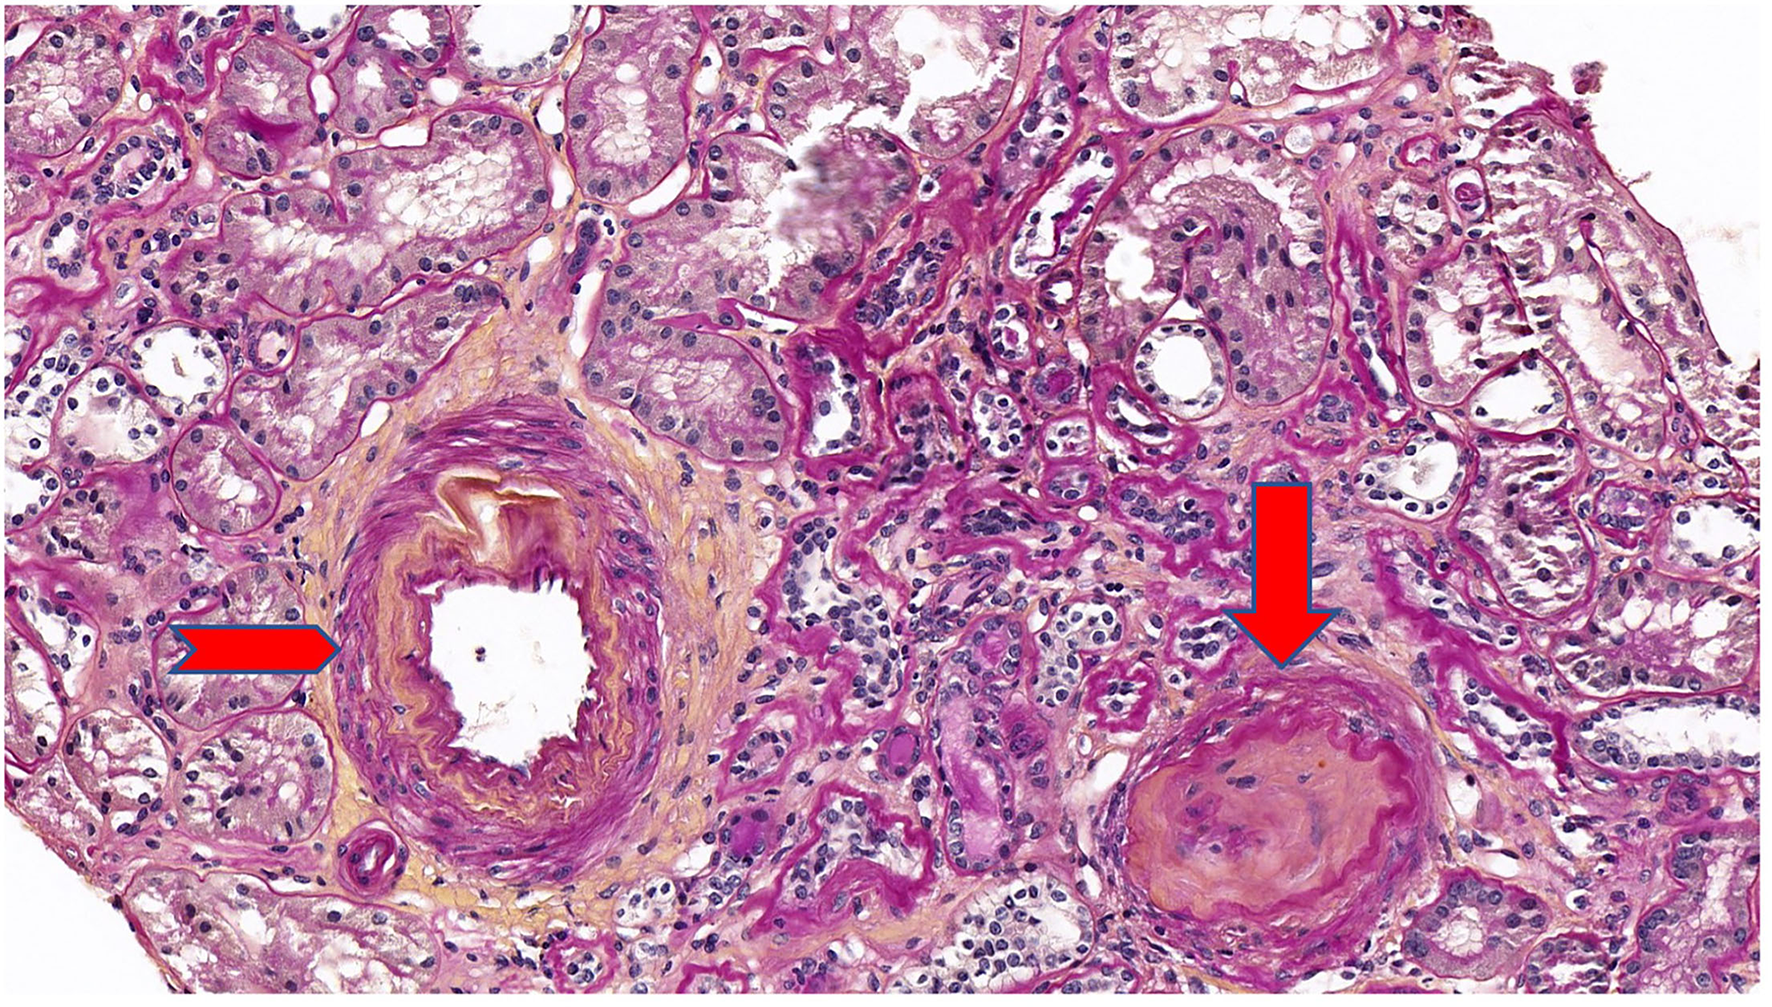

Five years after diagnosis, a serum creatinine of 2.79 mg/dL justified a kidney biopsy. Light microscopy (Figure 3) showed six glomeruli, five of which were within normal limits while one presented advanced sclerosis. Lesions of mild interstitial fibrosis and tubular atrophy were described. Arteries showed moderate arteriosclerosis (Figure 4). Immunofluorescence staining and electron microscopy have not been performed because frozen and glutaraldehyde fixed tissue were not available. An episode of pre-eclampsia occurred during the same year, leading to delivery at 26 weeks and post-natal death of twins.

Figure 4

Periodic acid Schiff (PAS) stain at ×20 magnification on light microscopy showing a mild interstitial fibrosis and tubular atrophy. One glomerulus out of 6 showed a complete sclerosis (arrow). Arteries showed a moderate arteriosclerosis (arrowhead).